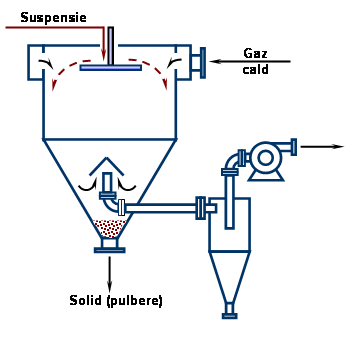

PULBERI FARMACEUTICE

PULBERI FARMACEUTICE Definitie: Pulberile pot fi definite din punct de vedere tehnologic si din punct de vedere fizico chimic, adica al sistemului dispers pe care il reprezinta. Din punct de vedere tehnologic, definCiteste tot ... 7412 cuvinte